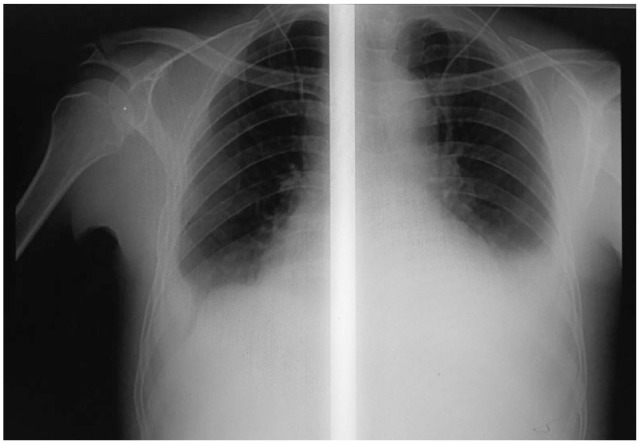

Case presentation: A 52-year-old male patient presented with generalized body swelling of 1 month duration associated with prolonged fever, malaise, fatigue, and lassitude. He had productive cough, dyspnea on mild exertion, and reddish discoloration of urine. Upon physical examination, blood pressure (BP) = 140/90 mmHg, pulse rate (PR) = 104 beats per minute, respiratory rate (RR) = 26 breaths per minute, temperature (T0) = 38.3°C, and Sp02 = 90% at ambient air. He had signs of bilateral pleural effusion. Cardiovascular examination revealed tachycardia, raised jugular venous pressure, murmurs of pulmonic regurgitation, and tricuspid regurgitation. There was grade 2 ascites and bilateral leg edema. On laboratory investigation, there were normochromic, normocytic anemia; raised ESR; positive Rheumatoid factor, elevated serum creatinine; and active urinary sediments on urinalysis. Two sets of blood culture were negative on days 1, 5, and 7. Chest-X-ray showed cardiomegaly with bilateral pleural effusion. ECG revealed sinus tachycardia with regular P-waves and QRS complexes. 2D Transthoracic echo showed vegetation on pulmonic valves, pulmonary valve lesions, dilated right atrium and right ventricle, and elevated right ventricular systolic pressure. Abdominal ultrasound revealed enlarged and echogenic kidneys, and ascites. Definitive diagnosis of PVE was made using modified Duke's criteria which was evidenced by 1 major (echo-proven vegetation on pulmonic valve), and 3 minors (suspected congenital pulmonic stenosis, fever, and immunologic phenomena [acute glomerulonephritis, positive rheumatoid factor]). The patient's clinical condition markedly improved after 2 weeks of intravenous antibiotics and loop diuretics, and discharged home after completing 6 weeks of parenteral antibiotics.